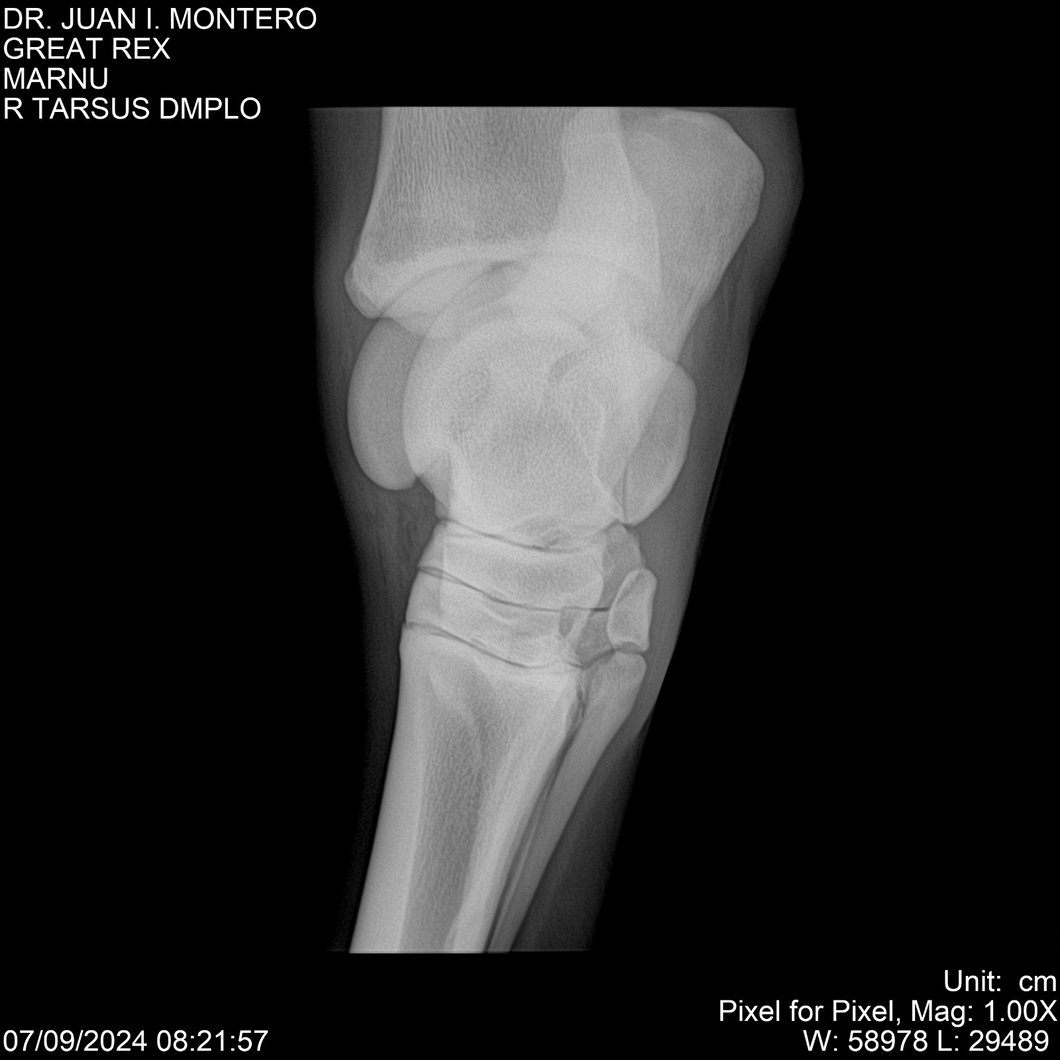

LOTE 4, GREAT REX Lote Anterior Volver al remate Lote Siguiente Ficha Contacto Montevideo - Ficha del Lote Identificador: #282518 Categoría: Yeguarizos Montevideo - 66 Visualizaciones ClicData Contacto Empresa: Abelenda N. R., Walter Hugo Nombre*: Teléfono* : E-mail* : Mensaje Enviar Registrese gratis Este contenido Exclusivo está disponible sólo para usuarios registrados Ingresar